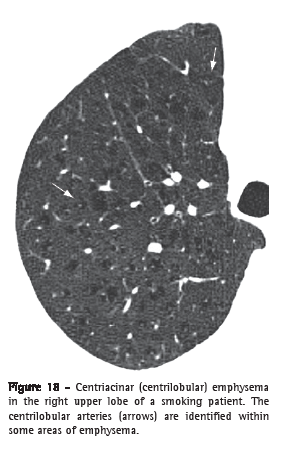

Centriacinar emphysema (enfisema centroacinar)

Centriacinar emphysema is the destruction of the walls of the centriacinar alveoli combined with an increase in respiratory bronchioles and associated alveoli. Centriacinar emphysema is the most common form of emphysema in cigarette smokers. Tomographic findings are centrilobular areas of decreased attenuation, usually without visible walls, having nonuniform distribution and predominantly located in the upper pulmonary regions (Figure 18).(37,38) The centrilobular arteries can frequently be identified within the hypodense areas. The term centrilobular emphysema is commonly used as a synonym in CT.